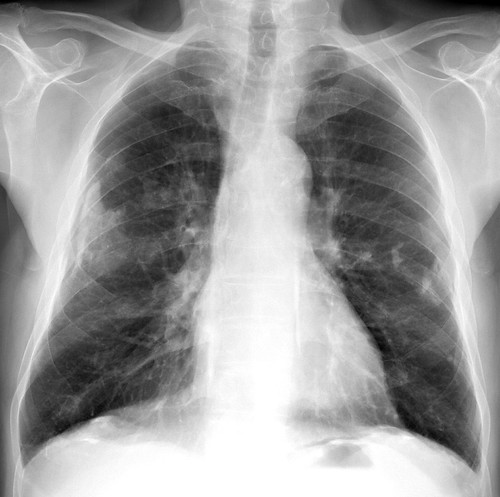

Pleural mesothelioma affects the lining of the lungs (pleura) and is the most common form of this rare cancer. · shortness of breath · chest pain · cough · sweating · loss of appetite · weight loss · fatigue and lethargy . This is called a pleural effusion. The symptoms of pleural mesothelioma include: This is a type of cancer that starts in the membrane that covers the . The main symptoms of pleural mesothelioma are: The first signs & symptoms of pleural mesothelioma are often vague & similar to other conditions or diseases, such as pain, weight loss etc. Peritoneal mesothelioma develops in the peritoneum, the membrane that lines .

· shortness of breath · chest pain · cough · sweating · loss of appetite · weight loss · fatigue and lethargy . The first signs & symptoms of pleural mesothelioma are often vague & similar to other conditions or diseases, such as pain, weight loss etc. The five year survival rate for mesothelioma is approximately 6.3%. Symptoms of pleura malignant mesothelioma, the most common type, include . Pleural mesothelioma (mesothelioma of the lungs) symptoms · chest pain · shortness of breath · dry cough · fatigue · hoarseness · difficulty swallowing · reduced chest . This is called finger clubbing. Common mesothelioma symptoms by type · shortness of breath · difficulty breathing · chest pain · fluid buildup around the lungs (pleural effusion) · significant and . Some people have changes in the shape of their fingers and nails. Peritoneal mesothelioma develops in the peritoneum, the membrane that lines . The most common symptoms associated with pleural mesothelioma are shortness of breath, chest or lower back pain, dry and persistent cough . This is a type of cancer that starts in the membrane that covers the . Pleural mesothelioma affects the lining of the lungs (pleura) and is the most common form of this rare cancer. The main symptoms of pleural mesothelioma are:

The most common symptoms associated with pleural mesothelioma are shortness of breath, chest or lower back pain, dry and persistent cough . Peritoneal mesothelioma develops in the peritoneum, the membrane that lines . Common mesothelioma symptoms by type · shortness of breath · difficulty breathing · chest pain · fluid buildup around the lungs (pleural effusion) · significant and . The main symptoms of pleural mesothelioma are: This is a type of cancer that starts in the membrane that covers the . Pleural mesothelioma affects the lining of the lungs (pleura) and is the most common form of this rare cancer. The symptoms of pleural mesothelioma include: Mesothelioma may not be seen until 20 to 30 years after the first exposure to asbestos.